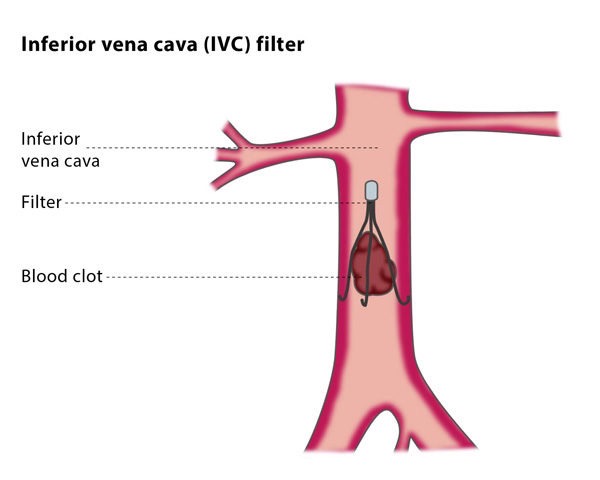

فیلتر ivc قلبی یا فیلتر ورید اجوف تحتانی (Inferior Vena Cava Filter یا IVC Filter) یک دستگاه پزشکی کوچک است که در ورید اجوف تحتانی (IVC) قرار میگیرد تا لختههای خون را قبل از رسیدن به ریهها گیر بیندازد و از آمبولی ریوی (PE) جلوگیری کند. این فیلترها عمدتاً برای بیمارانی استفاده میشوند که VTE (ترومبوآمبولی وریدی) دارند اما نمیتوانند از ضد انعقادها استفاده کنند، مانند موارد خونریزی فعال یا جراحیهای پرخطر.

فیلتر ivc قلبی به دستههای دائمی، قابل بازیابی (retrievable)، convertible و bioconvertible تقسیم میشوند. اکثر مدلها از مواد مانند Nitinol یا stainless steel ساخته شدهاند و شکل مخروطی یا cage-like دارند.

• موقعیت ایدهآل فیلتر: درست زیر وریدهای کلیوی (infrarenal) برای جلوگیری از انسداد